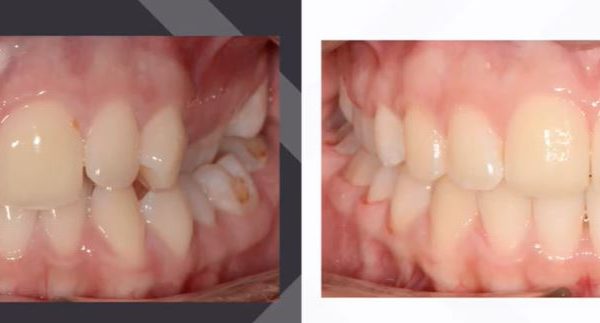

Az elmúlt évekből rengeteg szakmai referenciát tudnánk bemutatni, amelyek különböző fogszabályozási problémákat oldottak meg. Válogatva a több száz esetből, ezen az oldalon olyan képeket, információkat igyekeztünk bemutatni, amelyeknek a segítségével a jövőbeni pácienseinknek azt tudjuk üzenni: A Te fogsorod is lehet gyönyörű!

(Képeket a Pácienseink külön írásos beleegyezésével mutatjuk be!)